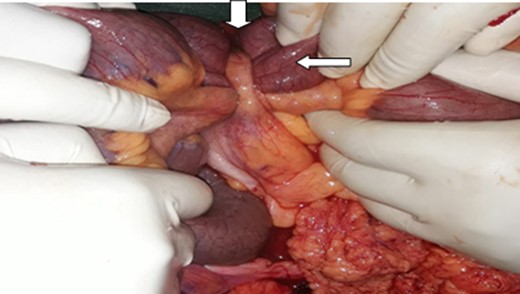

A midline laparotomy was performed. The intra-operative findings were intact 30 weeks sized gravid uterus, an inflamed appendix encircling the distal ileum (30 cm from the ileo-cecal valve). The tip of the appendix was adherent to the posterior peritoneum medial to the cecum. (Fig. 1). A lower uterine segment cesarean section was done. An alive male neonate weighing 1.8 kg with an APGAR score of 7 and 8 at the first and fifth minutes delivered. After uterus was closed, the appendix tip was gently released from the peritoneum which freed the ileum (Fig. 2). Appendectomy completed the operation. The baby treated in neonatal intensive care unit. Post-operatively, patient had an uneventful recovery and discharged on the fifth day after operation. In the first three post operative months the patient and the infants were in good health.

Intra-operative picture, Note the appendix (down arrow) making a knot around the distal ileum (side arrow).